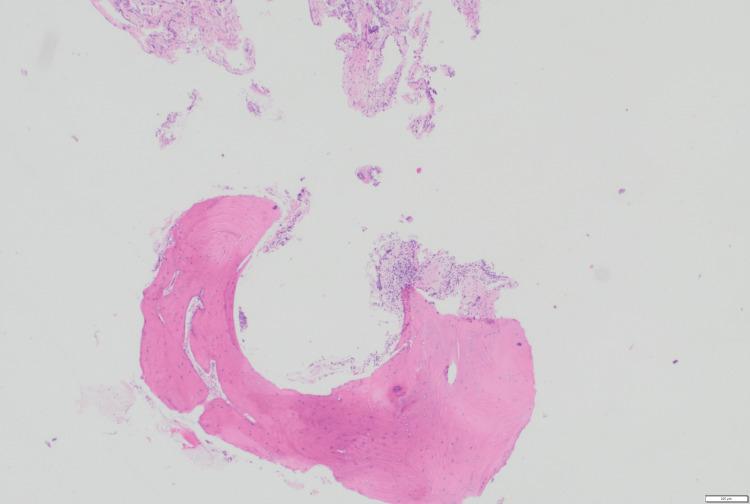

Tracheobronchopathia osteochondroplastica (TPO) is a rare, benign condition characterized by submucosal osseocartilaginous nodules sparing the posterior tracheal wall. We report a unique case of a 45-year-old male with a history of smoking, gastroesophageal reflux disease (GERD), and papillary thyroid carcinoma, in whom TPO was incidentally discovered during intraoperative bronchoscopy for hemithyroidectomy. The patient was asymptomatic from a respiratory standpoint, but bronchoalveolar lavage identified and methicillin-resistant (MRSA), suggesting a possible role of chronic infection in TPO pathogenesis. Diagnosis was confirmed through imaging and histopathology, revealing typical tracheal nodularity with no airway obstruction. No specific treatment was required for TPO, and the patient was managed conservatively with antibiotics for airway colonization. This case highlights the importance of recognizing TPO during unrelated procedures to avoid misdiagnosis and supports the hypothesis of infection-driven chronic inflammation contributing to its development.

骨软骨化生型气管支气管病(TPO)是一种罕见的良性疾病,其特征是黏膜下骨软骨结节不累及气管后壁。我们报告了一例独特病例,一名45岁男性,有吸烟史、胃食管反流病(GERD)和乳头状甲状腺癌病史,在因半甲状腺切除术进行术中支气管镜检查时偶然发现了TPO。从呼吸角度来看,患者无症状,但支气管肺泡灌洗发现了耐甲氧西林金黄色葡萄球菌(MRSA),提示慢性感染可能在TPO发病机制中起作用。通过影像学和组织病理学确诊,显示典型的气管结节状且无气道阻塞。TPO无需特殊治疗,患者通过使用抗生素治疗气道定植进行保守处理。该病例强调了在无关手术过程中识别TPO以避免误诊的重要性,并支持感染驱动的慢性炎症导致其发展的假说。